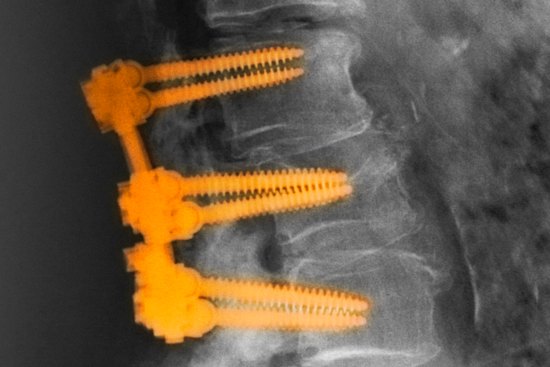

‘Dracula in the blood bank’: Years of inappropriate billing for spine surgery revealed

Many surgeons have been inappropriately billing Medicare and private health insurers for expensive spinal surgery, a leading surgeon claims.